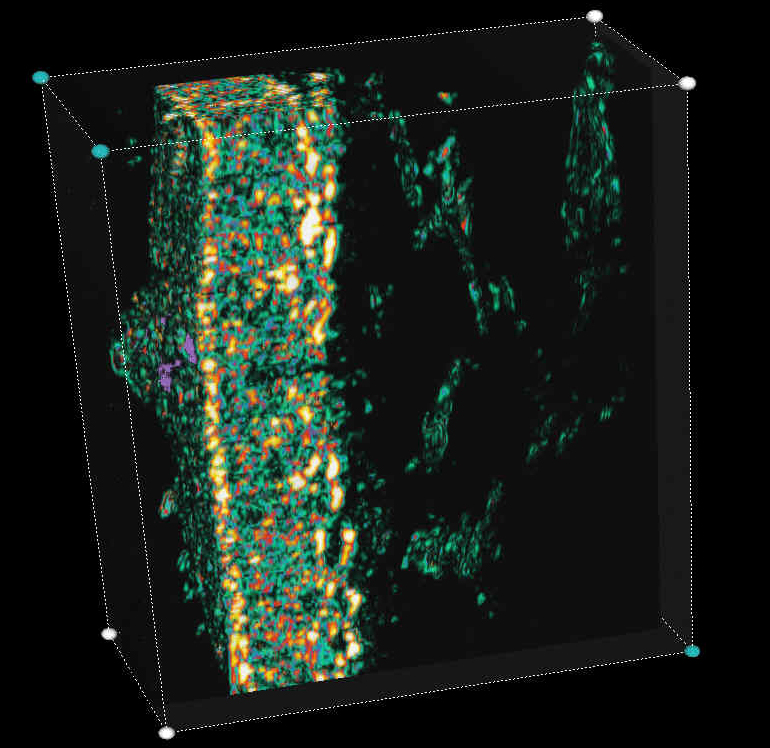

20 MHz 3D images

| Misc. |  Cellulite, arm |

Microdialysis tube |

Intradermal nevus |

Highlight. intrad. nevus |

| Misc. |  Ageband, forearm |

Nevus, skin parallel cut |

Normal, overlying hairs |